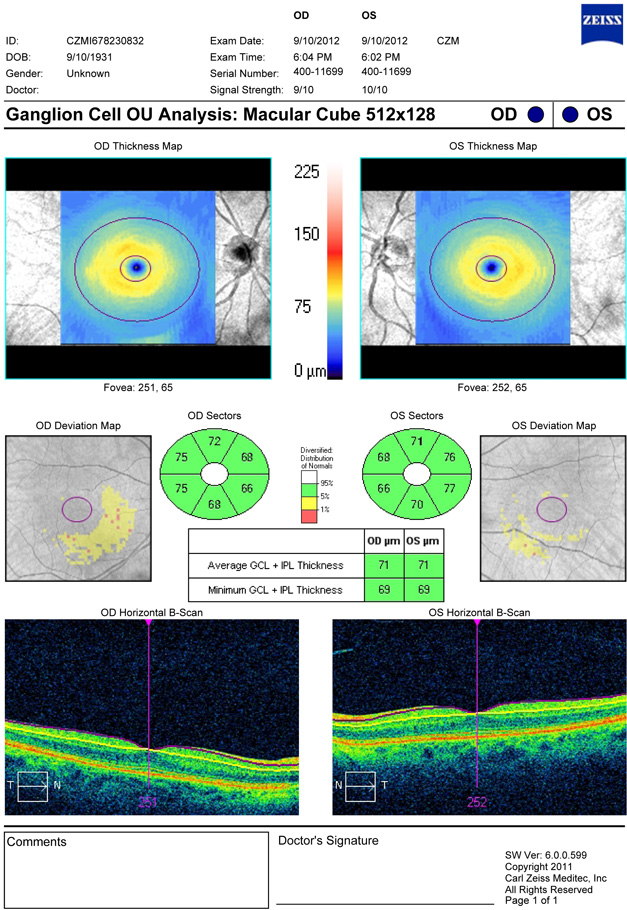

Görme sinirinde glokoma bağlı olarak ortaya çıkan değişiklikleri saptamak için duyarlı bir yöntem “Optik koherens tomografi-OCT”.

OCT ise tümüyle objektif bir tanı yöntemi olup lazer ışını yardımıyla görme sinirinde glokoma bağlı olarak ortaya çıkan değişiklikleri duyarlı ve güvenilir olarak gösterebilmektedir. Benim OCT ile ilk tanışmam 1996 yılında ABD’de Boston kentinde Tufts Üniversitesindeki “New England Medical Center”’da oldu. Burada dünyadaki ilk prototip cihaz ile çalışmalar yaptım, ve dünyadaki ilk ticari cihazlardan birini 1997 yılında Türkiye’ye getirerek kullanmaya başladım. OCT teknolojisindeki gelişmeler baş döndürücü hızla devam etti, cihazın duyarlılığı gelişti ve hızı arttırıldı. Günümüzde OCT glokomun erken tanısı için altın standart olarak kabul edilmektedir. Muayenehanemizde spektral teknolojiyle çalışan ve göz bebeğini genişletmeden teşhis olanağı sağlayan Zeiss Cirrus HD cihazı kullanılmaktadır.

OCT'nin erken tanı için referans olmasının nedeni glokomda saptanabilen en erken bozukluğun görme sinirinde ortaya çıkması ve OCT cihazının da bu hasarı güvenilir olarak gösterebilmesidir. Görme alanı muayenesi ile ancak sinir hücrelerinin %30-40'ı tahrip olduktan sonra glokom teşhis edilebilmektedir. OCT ise çok daha erken devrede (%10 hasar gibi) glokomun teşhisini mümkün kılmaktadır. OCT ayrıca glokom tanısı konmuş hastalarda takip sırasında gelişebilen bozuklukları da görme alanı muayenesine göre daha erken saptama olanağı sunmaktadır.